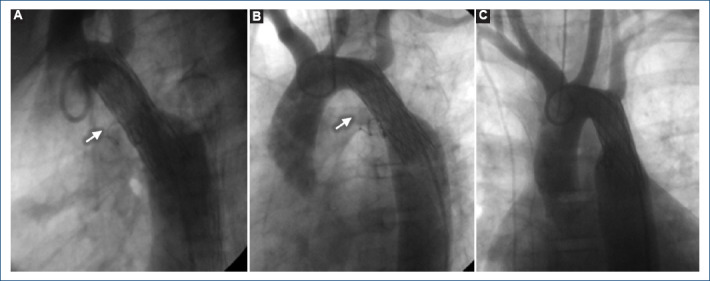

[Percutaneous treatment of aortic coartation and ductus arteriosus in a patient with Ebstein's anomaly].